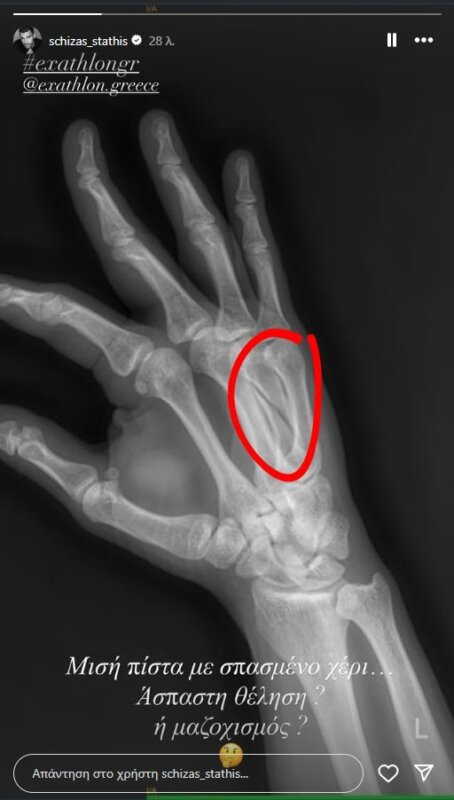

Δευτερόλεπτα αφού επισημοποιήθηκε η αποχώρησή του ανέβασε στο Instagram post με την ακτινογραφία που έβγαλε και δείχνει ξεκάθαρα το τι ακριβώς έχει συμβεί.